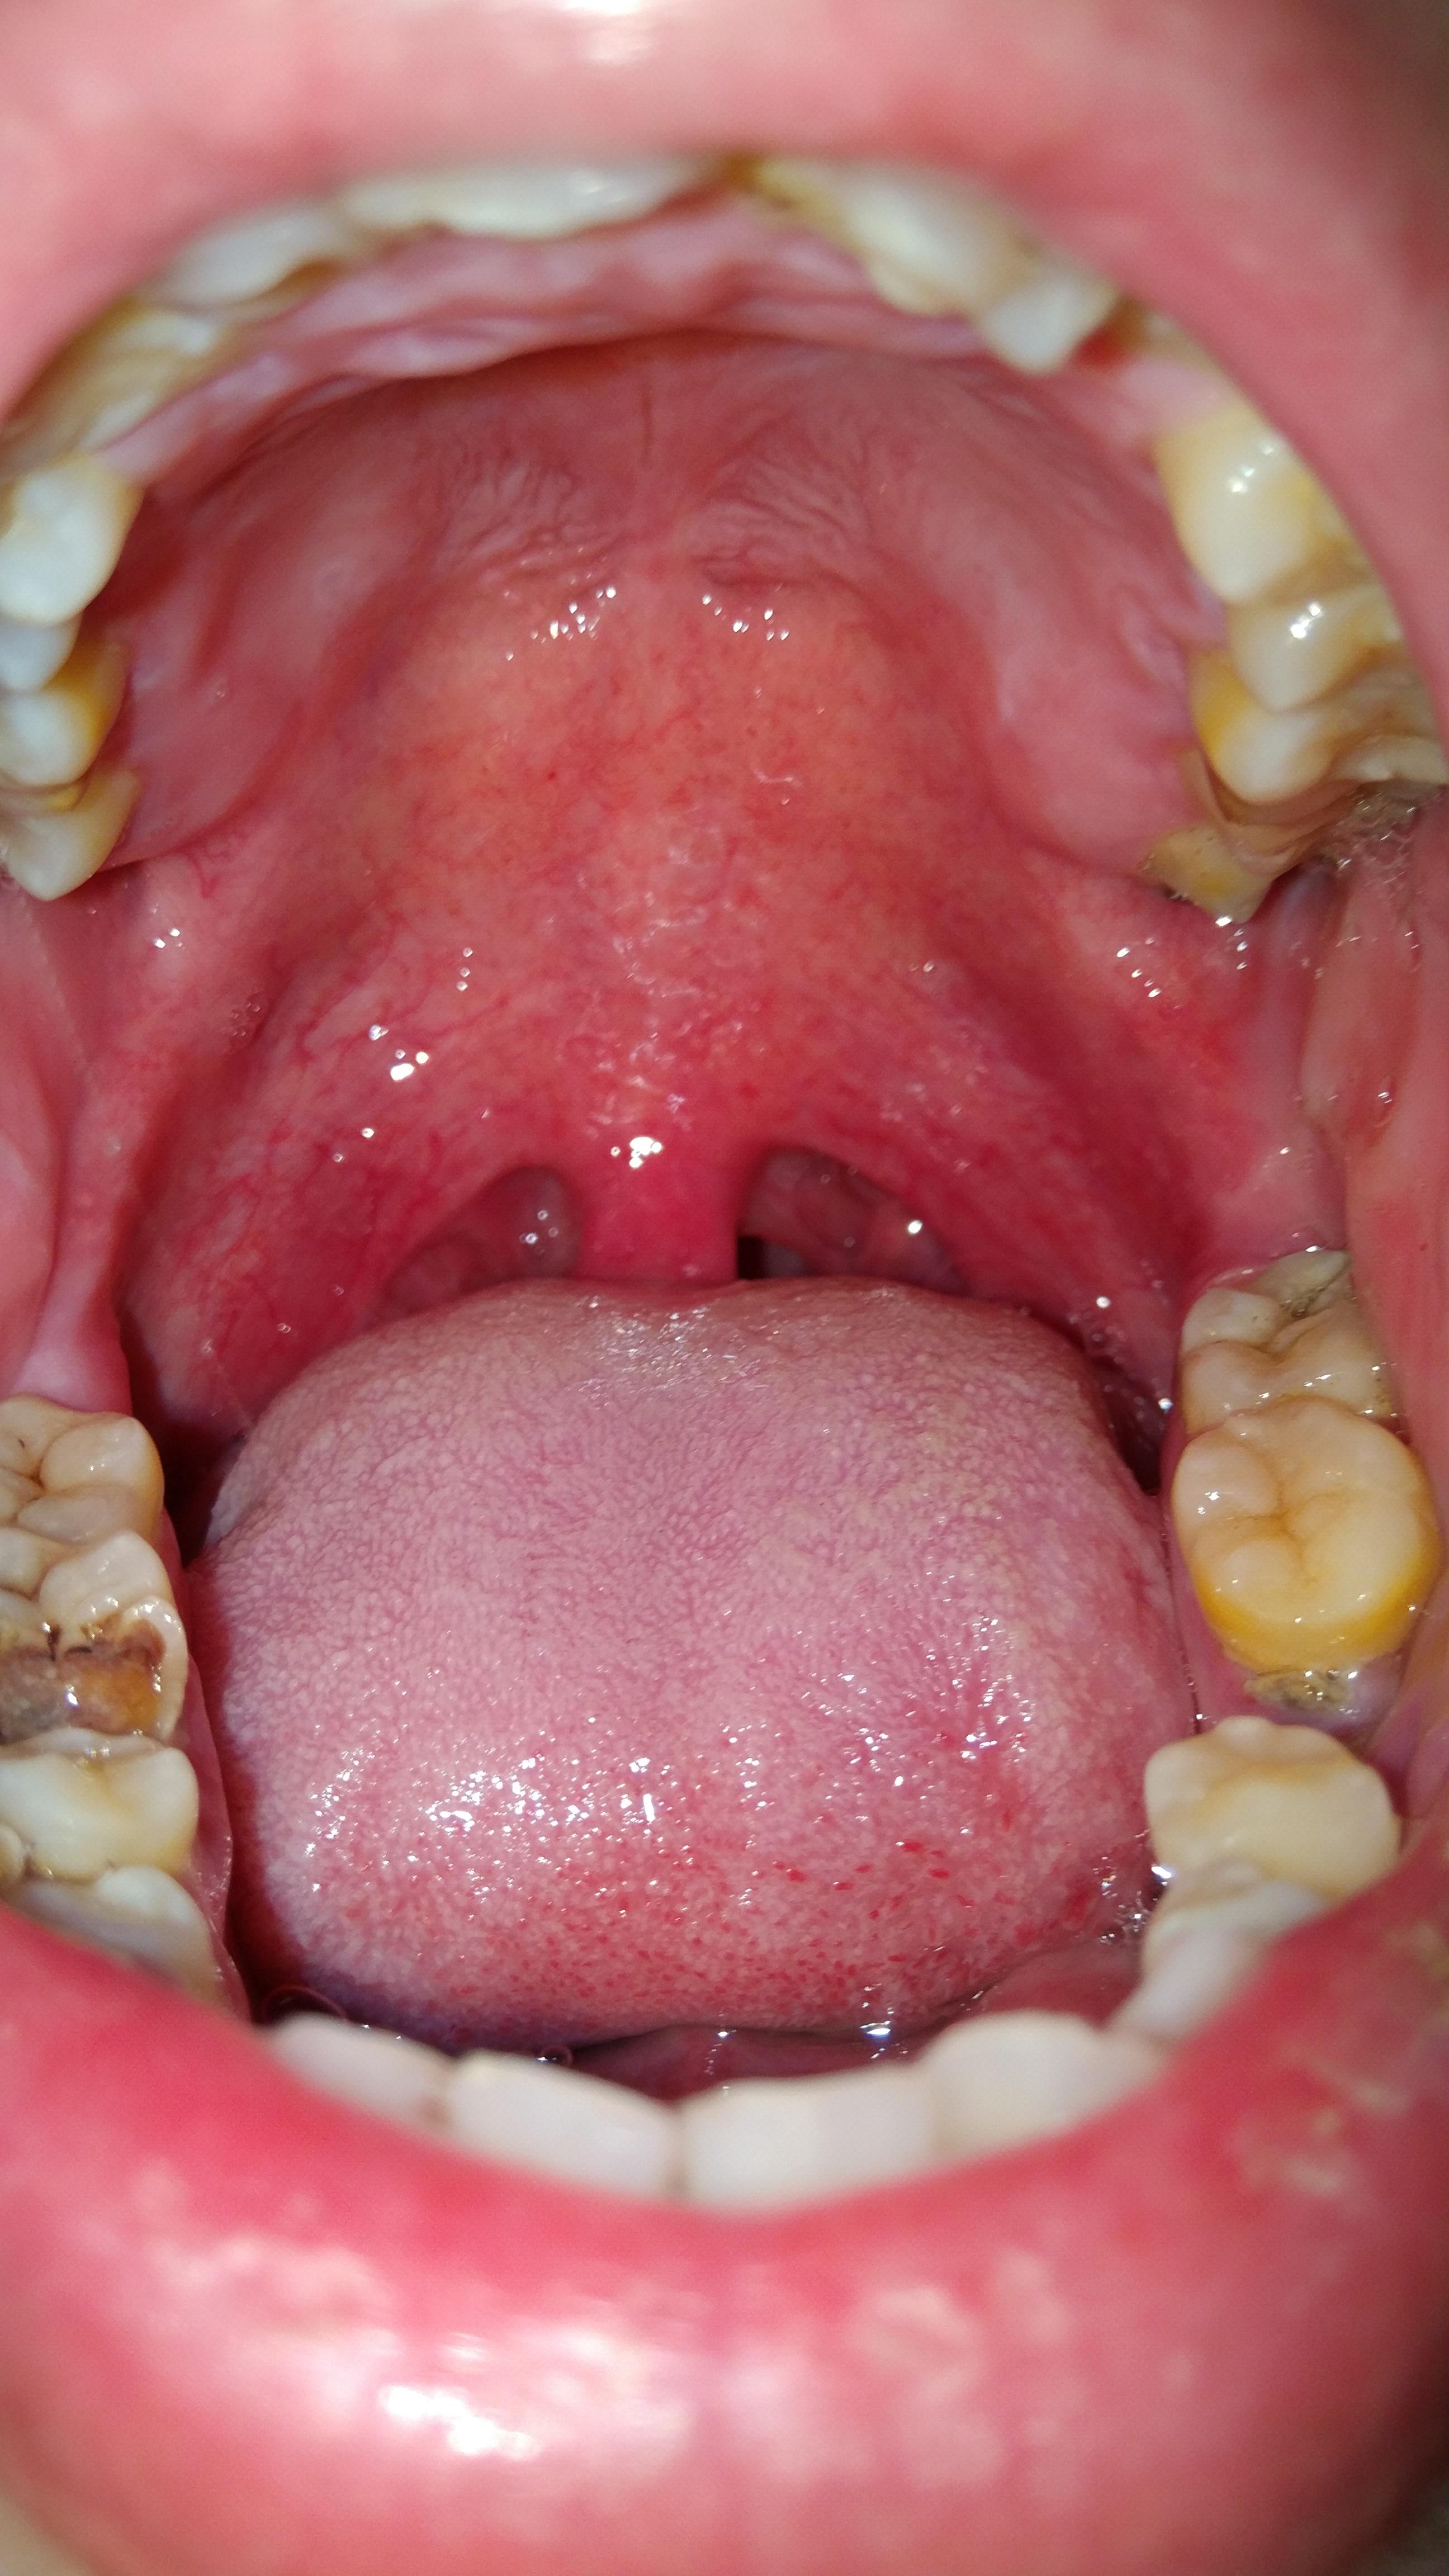

顺便拍了一下全口腔,除了蛀牙,掉牙。牙不齐,牙身还好黄,从前就不注意护理牙齿,感觉好自卑了。。。图片都可以拿去教育孩子了。。。